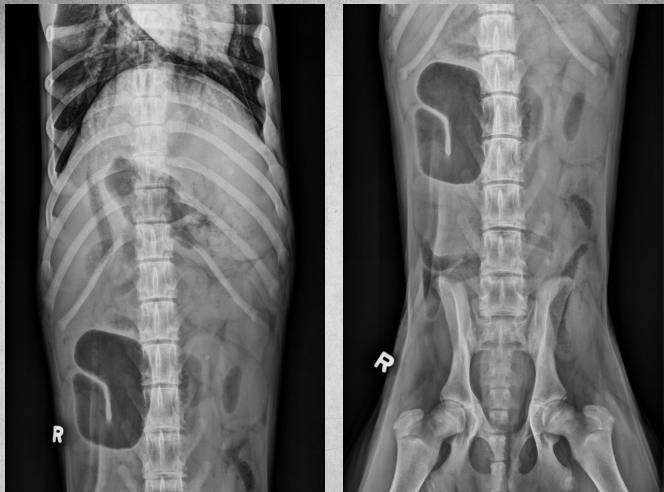

●9 yo female sterilized German

Shepherd

●Anorexia, lethargy

●Weakness

● Mass effect, bowels lifted dorsally

and caudally

● Round shadow cranially to tail of

the spleen

● Splenomegaly, splenic mass. hemangiosarcoma